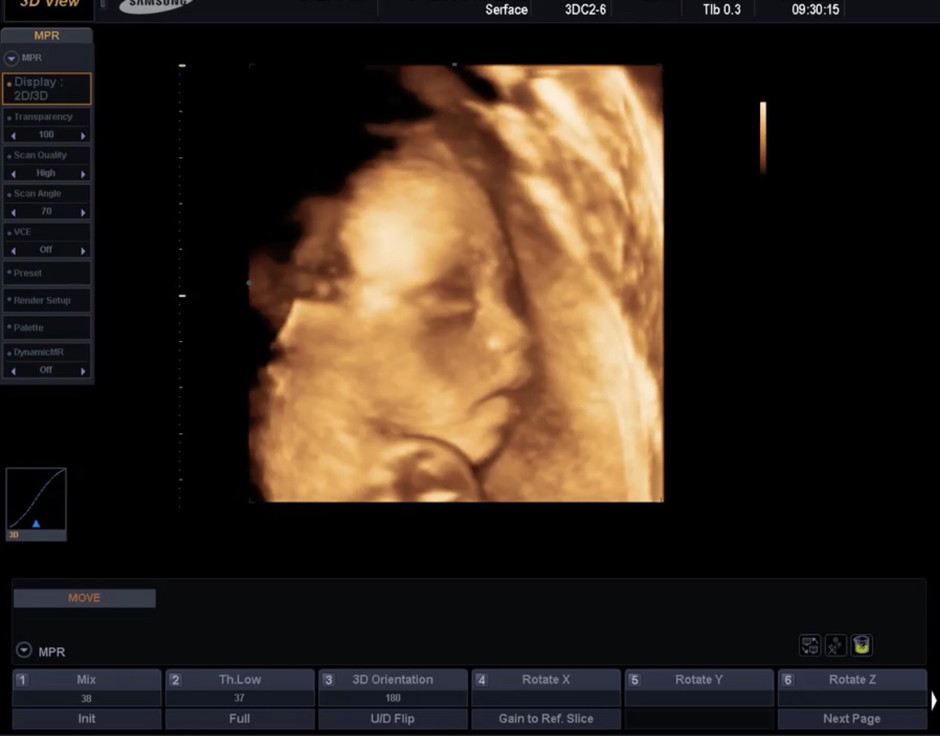

25week1d คะ ลูกสาว❤️

ภาพตอน 14 สัปดาห์จ้า